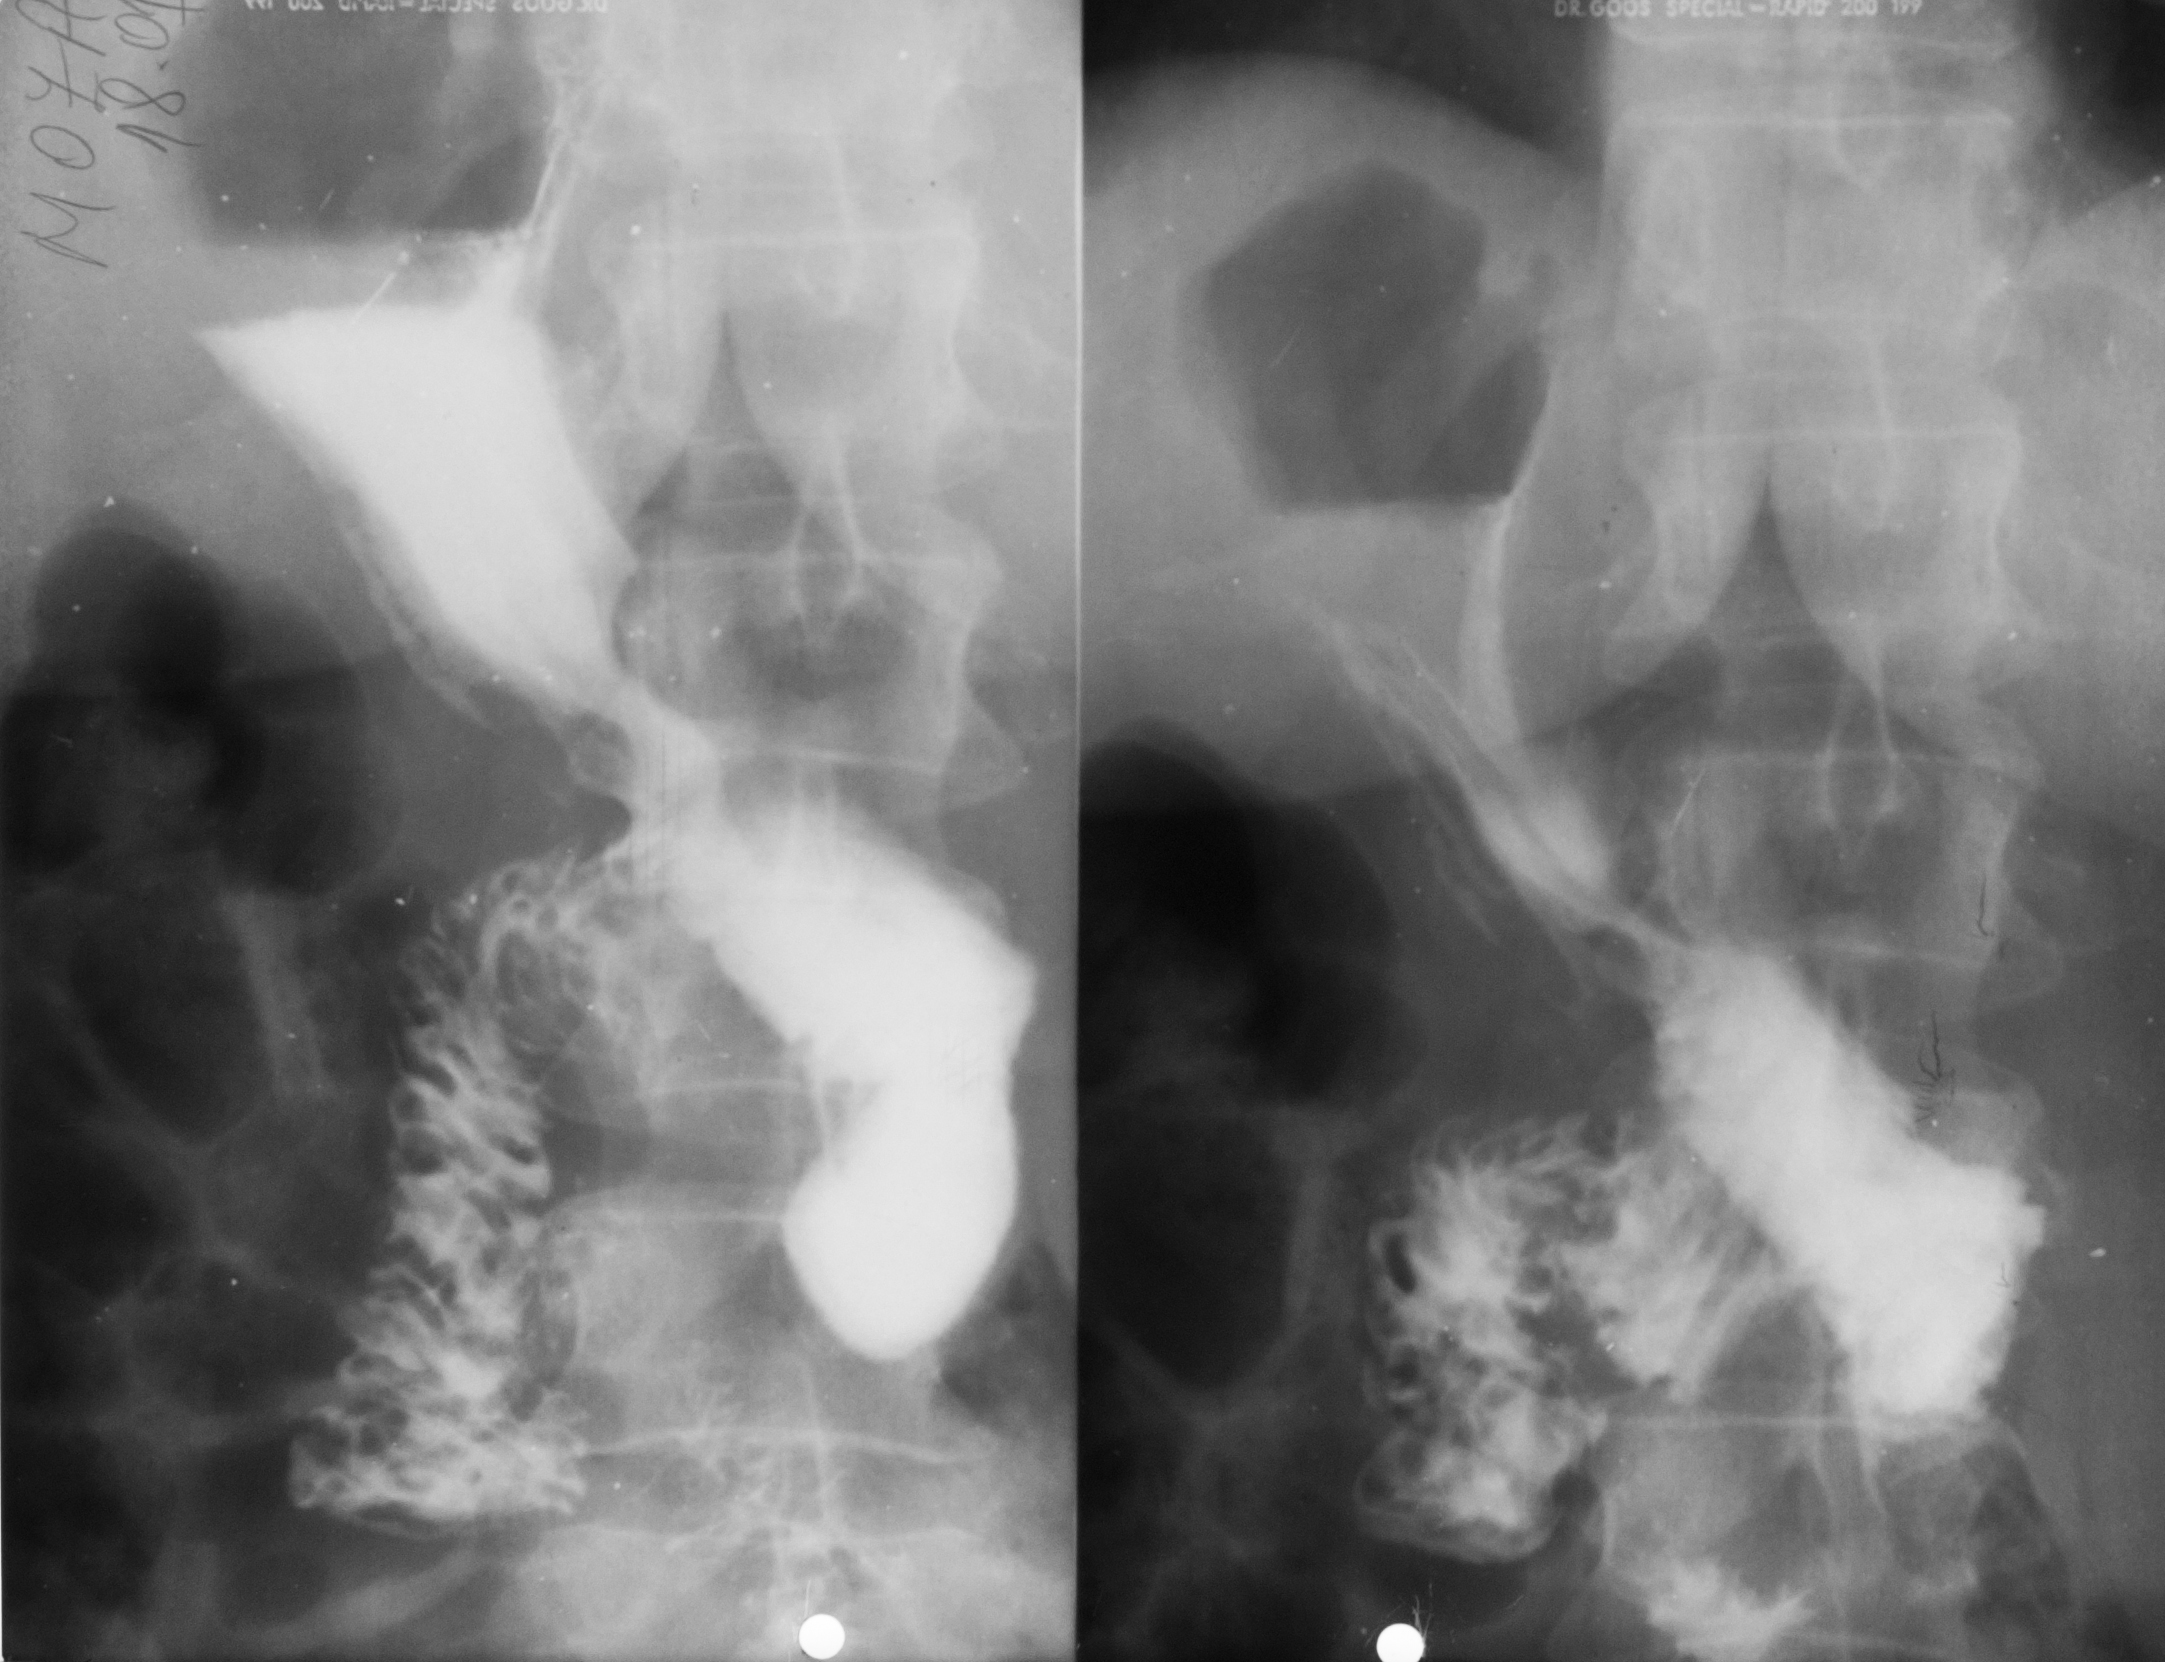

: NIȘA BENIGNĂ

Tranzit baritat la nivelul stomacului..La nivelul curburii mici se observă o imagine de adiție mai mult adâncă decât lată,cu pliuri de mucoasă ce converg spre zona respectivă

NIȘĂ BENIGNĂ

Nișă benignă mai mult adâncă decât lată,tot la nivelul micii curburi

ASPECT DE CLEPSIDRĂ AXIALĂ

Tranzit baritat cu aspect biloculat al corpului gastric:aspect de clepsidră axială(ceea ce înseamnă că în zona mediocorporeală se află un neoplasm infiltrativ)

ASPECT BILOCULAT AL CORPULUI GASTRIC

Tranzit baritat la nivelul corpului gastric cu incizură la nivelul curburii mari și aspect biloculat al corpului gastric:biloculare de tip benignă

Biloculare excentrică?

ASPECT BILOCULAT AL CORPULUI GASTRIC

Biloculare excentrică

NIȘĂ BENIGNĂ

Tranzit baritat la nivelul stomacului..Se observă o imagine de adiție,nișă de tip benign,mai mult adâncă decât lată

: NIȘĂ BENIGNĂ

Nișă benignă care iese din conturul gastric,mai mult adâncă decât lată

Prima imagine de la stânga:examinare în dublu contrast

A doua imagine:examinare în mono contrast

: STENOZĂ

Tranzit baritat cu stenozarea lumenului gastric la nivel corporeal și antral

Stenoză,cel mai probabil,de tip malign

NIȘĂ ÎN LACUNĂ

Examen baritat al corpului gastric

Se observă defecte de umplere,adică dislocuirea substanței de contrast de ceva ce se găsește în lumenul stomacului și anume o masa parenchimatoasă cu contur polilobat.

Cel mai probabil este un proces neoplazic vegetativ de dimensiuni mari,care are la nivelul ei și o ulcerație.Imaginea se numește nișă în lacună.

NIȘA MALIGNĂ ÎN REGIUNEA ANTRALĂ

Nișa malignă este mai mult lată decât adâncă și nu iese din conturul corpului gastric.

Ulcerația este în perete,dar nu iese din conturul peretelui gastric.

ULCERAȚIE CRONICĂ

Se observă,în urma tranzitului baritat,bulbul duodenal cu incizuri la nivelul curburilor,având aspect de treflă,caracteristic pentru ulcerațiile cronice

:NEOPLAZIE INFILTRATIVĂ

Tranzit baritat.Se observă o îngustare semnificativă a lumenului la nivel antral,dând aspect de antru amputat.Nu sunt vizibile pliurile de mucoasă,deci este vorba de o neoplazie infiltrativă.

NIȘĂ LA NIVELUL BULBULUI DUODENAL

Tranzit baritat.La nivelul bulbului duodenal se află o pată persistentă de substanță de contrast,captată la nivelul unei nișe

NIȘĂ DE TIP MALIGN

Nișă de tip malign mai mult lată decât adâncă,situate în regiunea antrală cu pliuri de mucoasă ce converg până în craterul nișei

Tranzit baritat.Bulbul duodenal cu o pată ce persistă pe una din fețele bulbului.Avem de a face cu o nișă de dimensiuni mari la nivelul bulbului